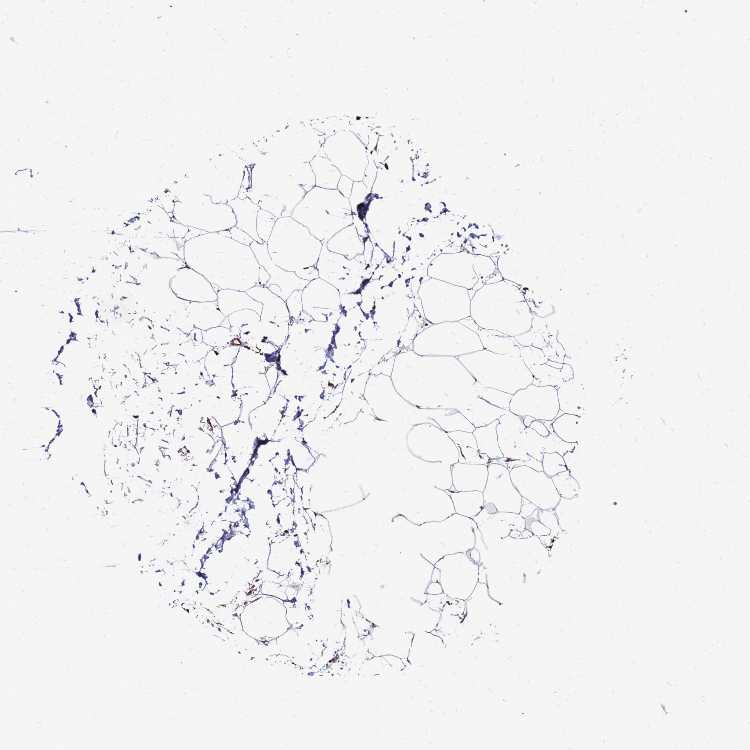

SOFT TISSUE 2 - Antibody stainingi

Antibody staining in the annotated cell types in the current human tissue is reported as not detected, low, medium, or high, based on conventional immunohistochemistry profiling in selected tissues. This score is based on the combination of the staining intensity and fraction of stained cells.

Each image is clickable and will lead to virtual microscopy that enables deeper exploration of all samples and also displays staining intensity scores, fraction scores and subcellular localization as well as patient and tissue information for each sample.

Antibody HPA023038

Fibroblasts Medium